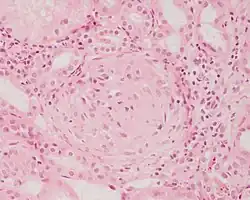

![]() Fotomikrografi af en nyrebiopsi fra en patient med glomerulonefritis. | |

Glomerulonefritis er en nyresygdom der sædvanligvis rammer begge nyrer og er karakteriseret ved betændelse af de små blodkar i nyrerne (glomeruli). Glomerulonefritis kan vise sig som blod i urinen (hæmaturi), protein i urinen (proteinuri), nefrotisk syndrom, eller som akut eller kronisk nyresvigt.